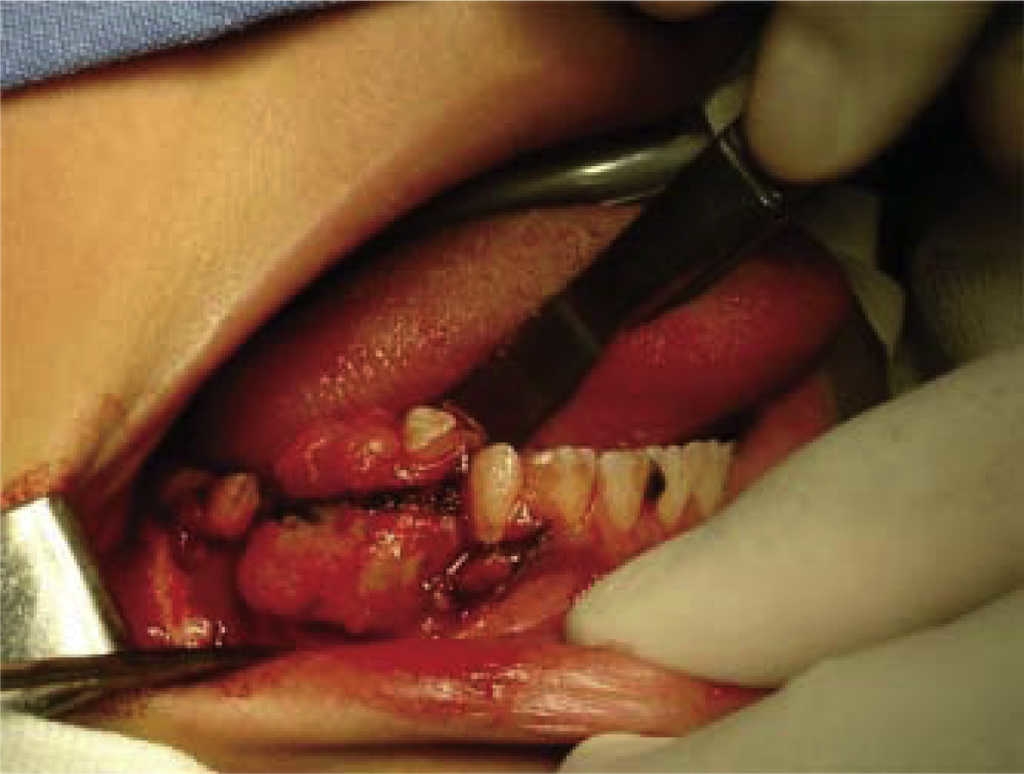

Paciente femenina de 13 años de edad la cual presenta lesión en proceso alveolar mandibular derecho, con tres meses de evolución, crecimiento rápido, dolor, ligera parestesia en el labio inferior derecho, lesión de aspecto granuloso, sangrante, con base sésil, se observa radiográficamente, área radiolucida, difusa, a nivel de premolares inferiores derechos (Figura 12). No presenta otros datos patológicos de importancia.

El resultado de biopsia reporta fibroma ameloblástico mandibular. Se realiza resección en bloque de la lesión conservando borde inferior (Figura 13).